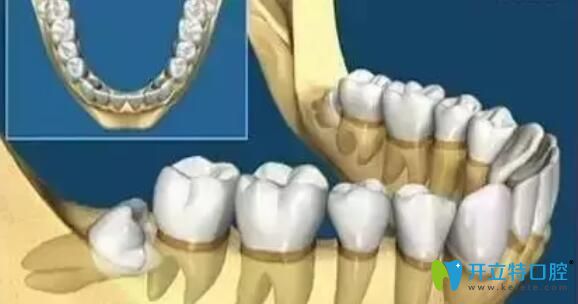

牙齒在頜骨內(nèi)由于位置不正,不能萌出到正常的咬合位置,這樣的牙齒稱為阻生牙。常見的阻生齒是下頜第三磨牙(智齒),其次是上頜第三磨牙(智齒)和上頜尖牙。所以阻生牙不一定是智齒,也可能是其它牙齒,如果智齒萌出正常,則不能稱為阻生牙。

智齒其實(shí)是從正中的門牙往里數(shù)的第八顆牙齒,一般比正常的牙齒出現(xiàn)的要晚,16歲到25歲才會(huì)出現(xiàn)。智齒如果位置長的端正,不影響健康不需要拔除,否則長得傾斜,偏倒,必須及時(shí)拔掉,一面帶來口腔問題。